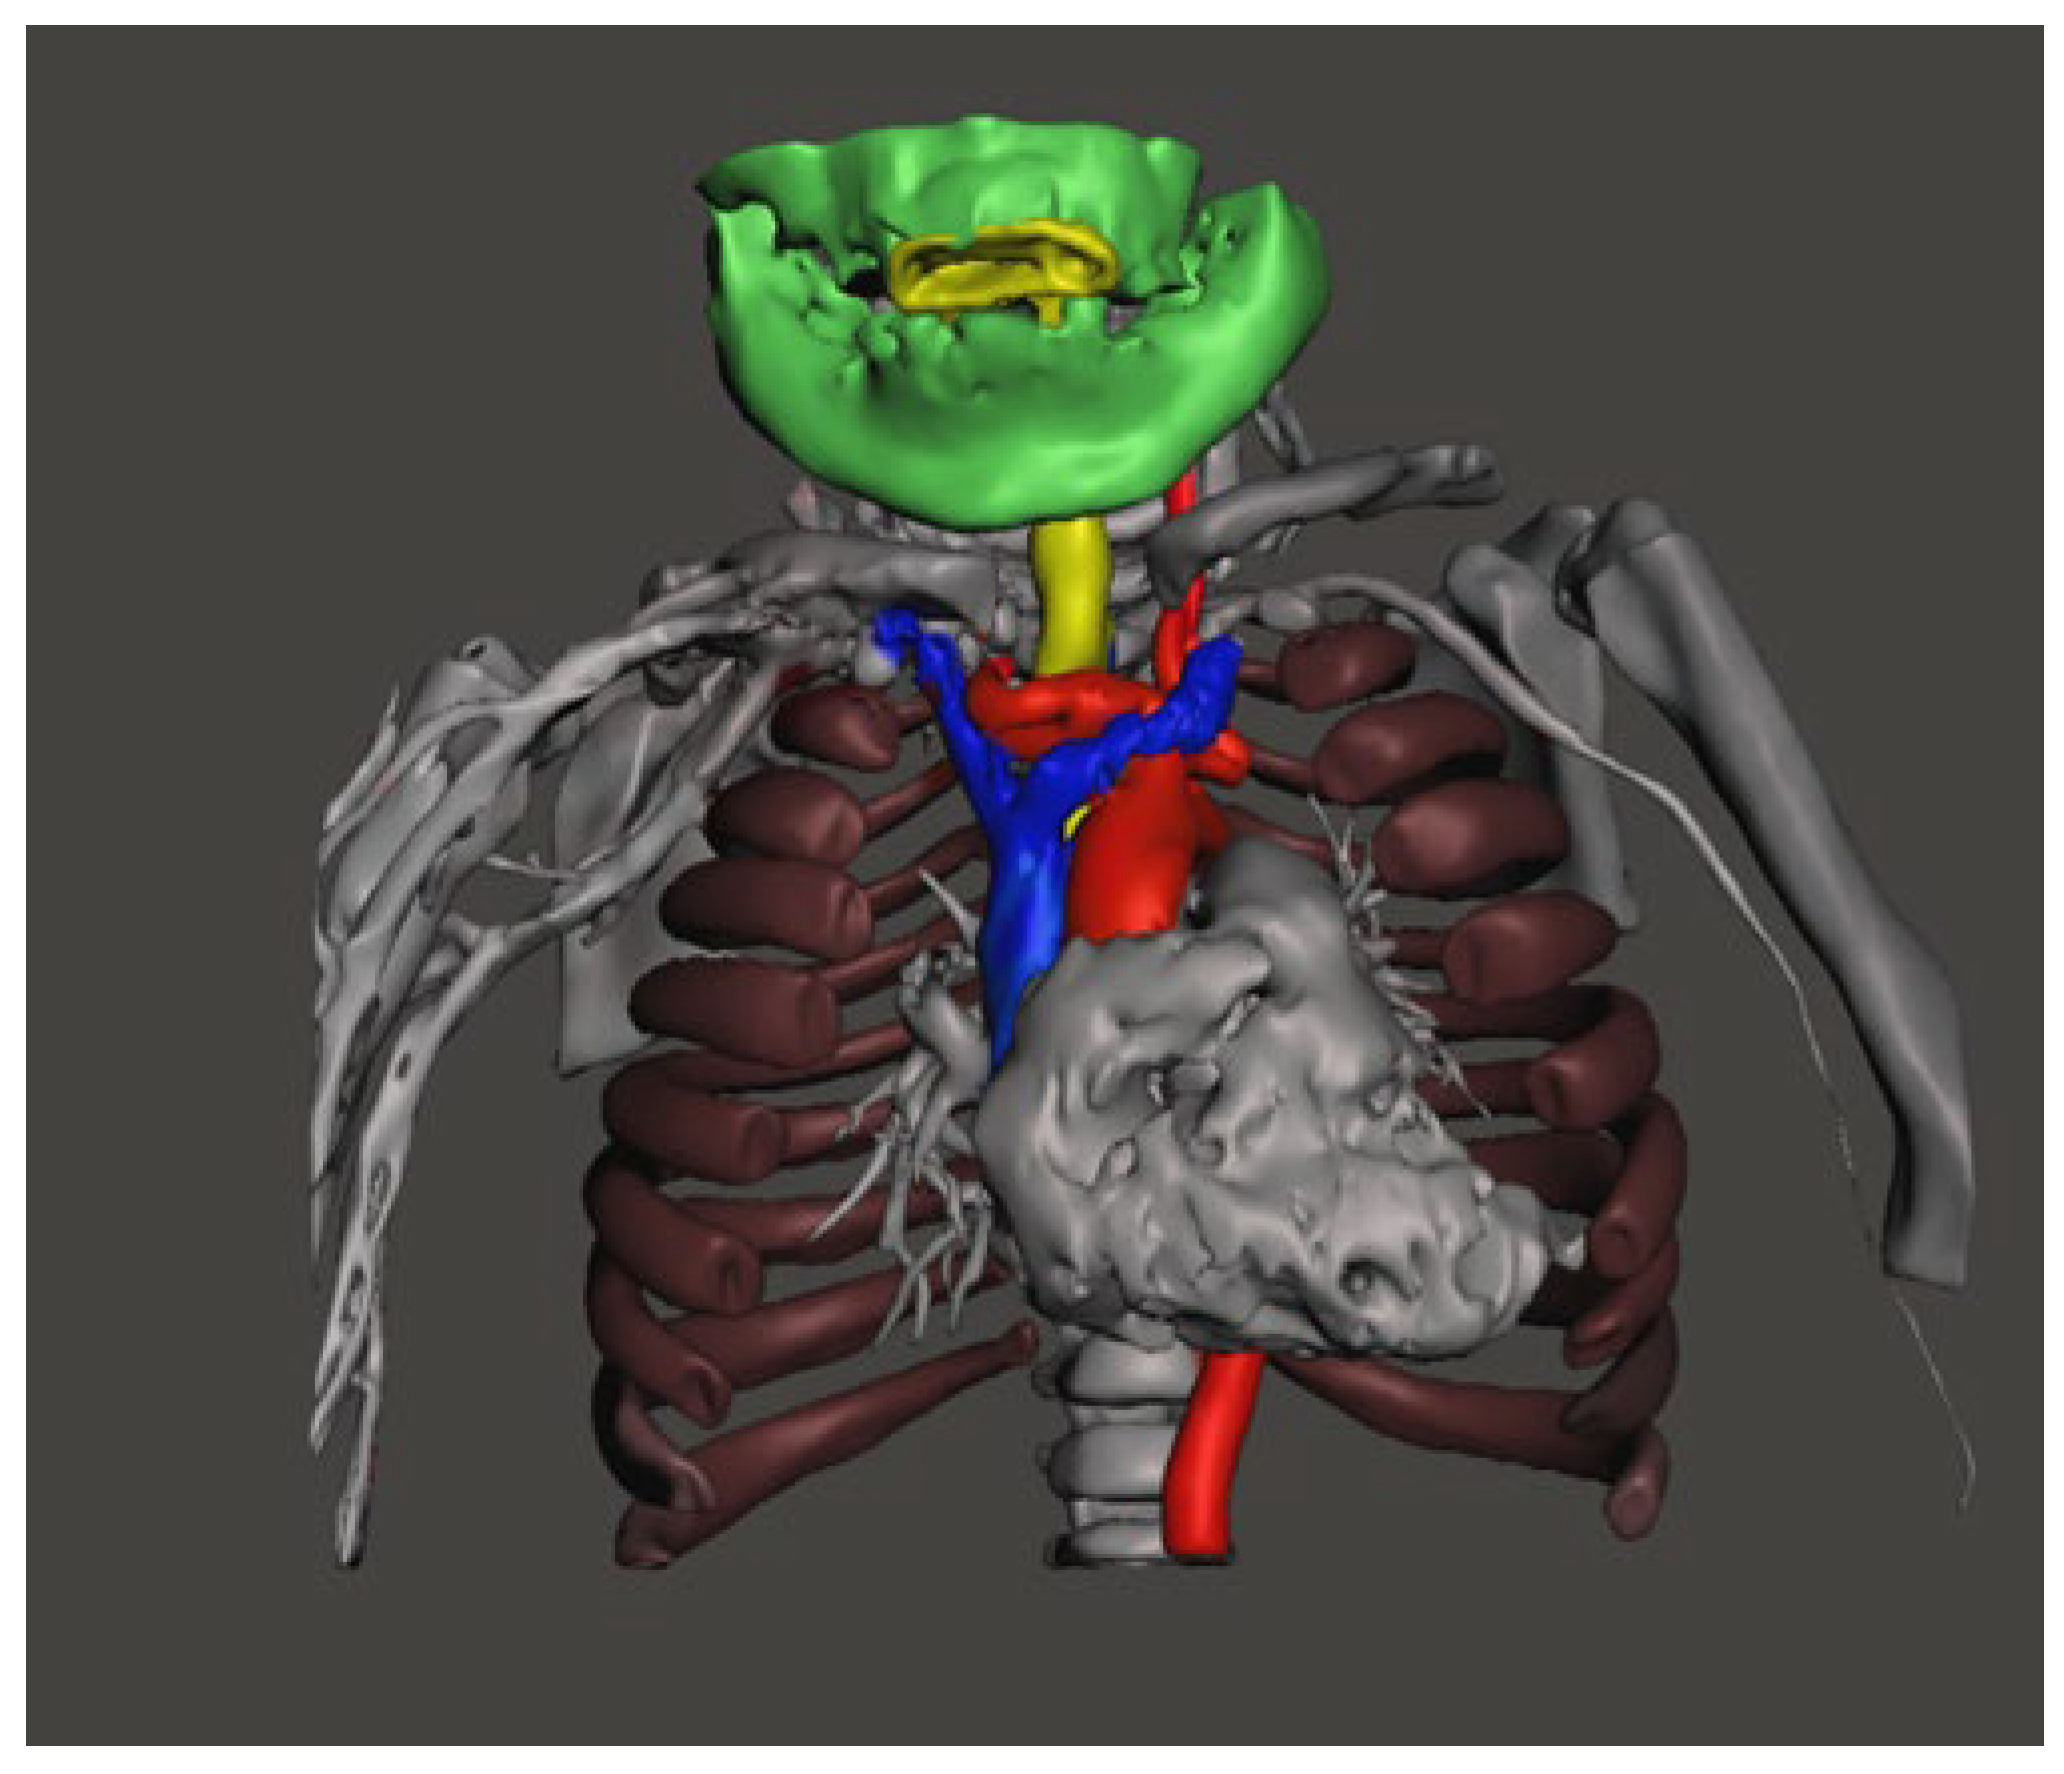

2. Ethical Issues

3. Case Presentation

4. Discussion